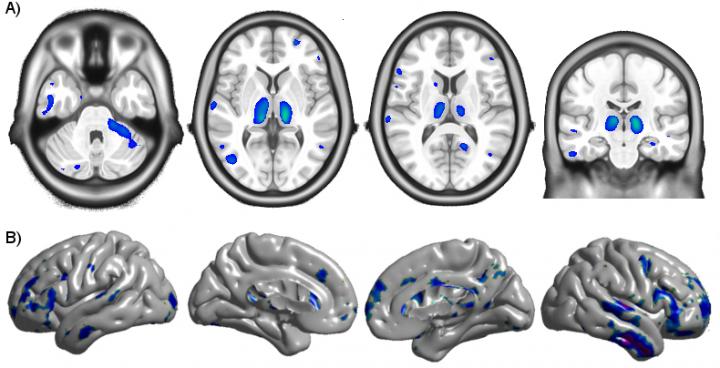

Scientists have known for some time that HIV-infection causes reduced volume and cortical thickness in some regions of the brain, but it was unclear when these changes begin and what role combination antiretroviral therapy (cART) plays in stopping or slowing its progression. To answer these questions, researchers from the Montreal Neurological Institute and Hospital (The Neuro) of McGill University, in collaboration with researchers from University of Washington St. Louis and Yale University, analysed magnetic resonance imaging (MRI) data from 65 patients at the University of California San Francisco who had been infected less than one year before.

They compared the MRI data to that of 19 HIV-negative participants and 16 HIV-positive patients who had been infected for at least three years. The researchers found that the longer the duration of untreated infection, the greater the volume loss and cortical thinning in several brain regions. Once cART treatment began, the volume changes in these regions stopped, and cortical thickness increased slightly in the frontal and temporal lobe.